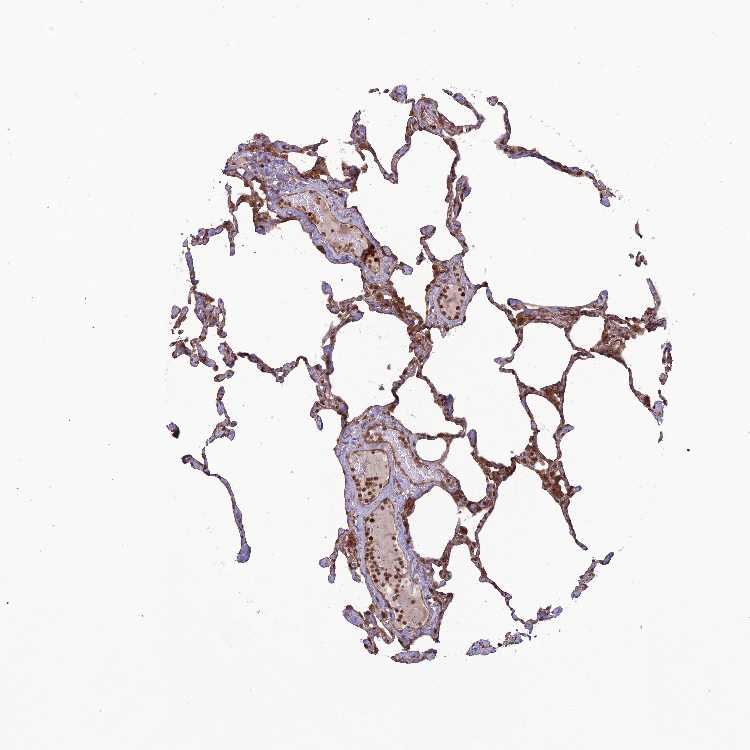

Antibody staining in the annotated cell types in the current human tissue is reported as not detected, low, medium, or high. This score is based on the staining intensity and fraction of stained cells.